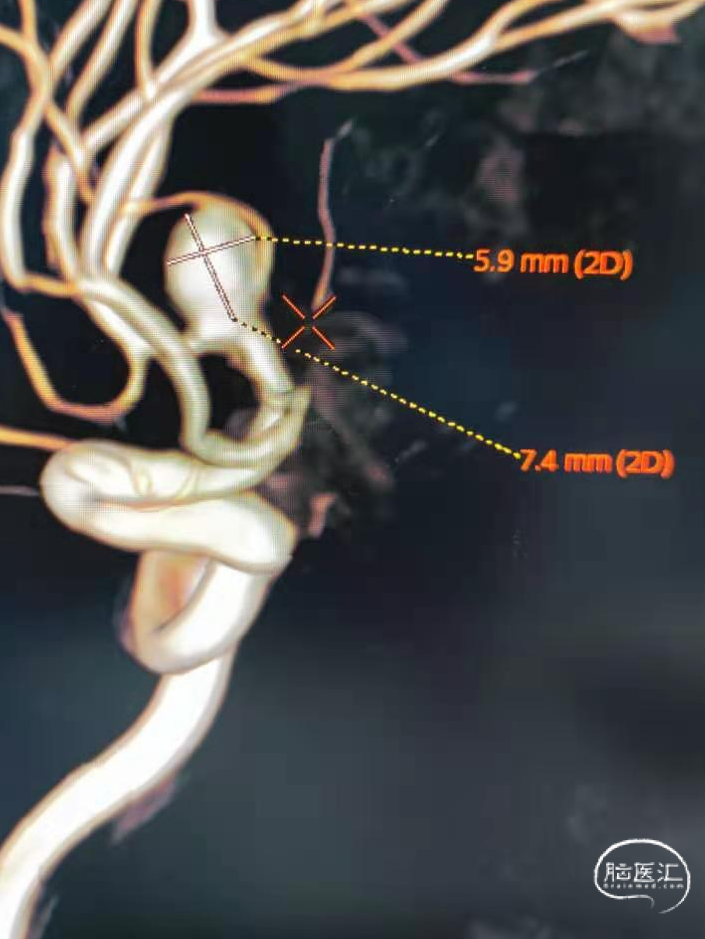

脑血管造影显示右侧大脑中动脉分叉部宽颈动脉瘤,约7.4-7.0-6mm大小。动脉瘤为不规则形态,右侧中动脉上下支干均受累,其中上支干纤细约1.0mm,自瘤体近瘤颈处发出。

术前影像

仔细分析动脉瘤与血管关系,我们最终选择单支架辅助。

但是单支架辅助栓塞存在支架放到哪支血管的问题:

如果放到下支干,到位容易且大部瘤颈可良好覆盖。但是靠近上支干部分可能存在栓塞不全。

如果放上支干,虽然瘤颈重建效果好,但存在支架导管到位困难、因上支干血管直径小支架打开困难等风险。另外下支干仍存在无法安全保护的可能。